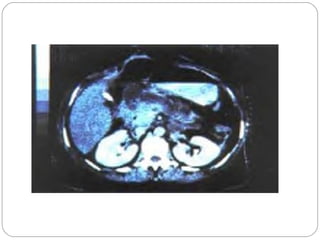

HALLAZGOS DE LA TAC

TAC sin contraste (Balthazar)

GGrraaddoo HHaallllaazzggooss SSccoorree

AA PPáánnccrreeaass nnoorrmmaall 00

BB AAuummeennttoo ddee ttaammaaññoo ffooccaall oo ddiiffuussoo 11

CC PPáánnccrreeaass aannoorrmmaall ccoonn iinnffllaammaacciióónn ppeerriippaannccrreeááttiiccaa 22

DD 11 ccoolleecccciióónn iinnttrraa oo eexxttrraappaannccrreeááttiiccaa 33

EE 22 oo mmááss ccoolleecccciioonneess oo ggaass rreettrrooppeerriittoonneeaall 44

Score de necrosis con TAC con

contraste

% ddee nneeccrroossiiss SSccoorree

00 00

<< 3300 22

3300--5500 44

>>5500 66

INDICE DE GRAVEDAD DE PANCREATITIS POR HALLAZGOS DE LA TAC

El índice da un score máximo de10.

Score Mortalidad

• 0 – 3 4%

• 4 – 6 35%

• 7 – 10 100%